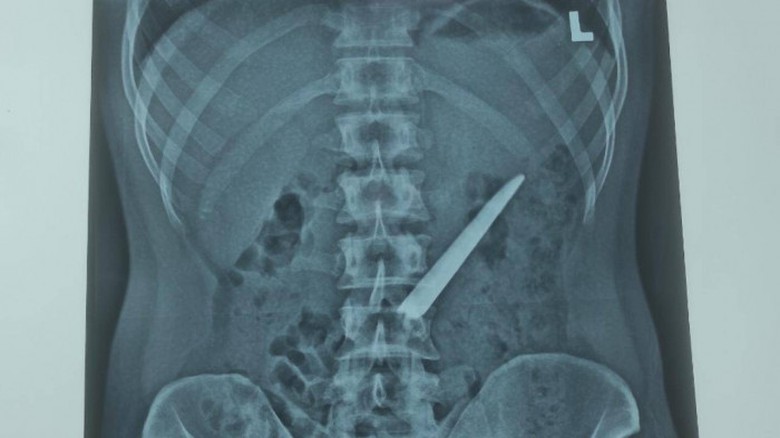

Hình ảnh chụp X-Quang cho thấy, lưỡi dao Thái Lan nằm trong bụng nam thanh niên ở Bạc Liêu. (Ảnh: BVĐK Bạc Liêu)

Sau khi thăm khám và nội soi, các bác sĩ phát hiện một vật sắt nhọn dài khoảng 10cm (lưỡi dao Thái Lan không có cán) nằm bên trong bụng đoạn giữa tá tràng.